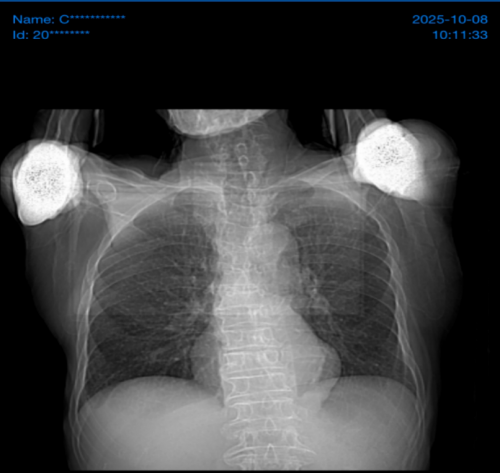

入院时胸片: